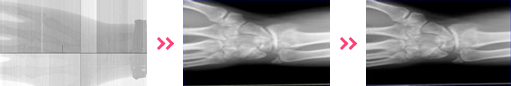

BTOZ의 의료영상처리 서비스는 Digital Flat Panel Detector에서 X-Ray Generator의 제어를 아우르는 매끄러운 영상 처리 기술을 제공합니다.

2D Image 처리 기술

Digital X선 영상의 Pre-Processing / Post- Processing 기술:

Calibration & Image Processing